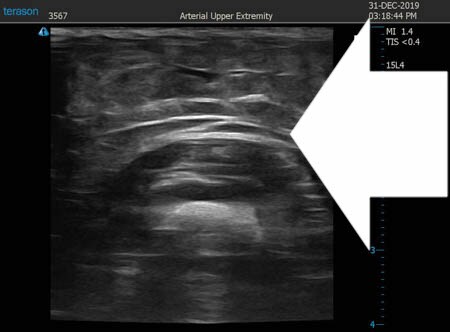

いつものように3Dタッチビュー(超音波)で

皮下脂肪層を評価してみましょう。

右二の腕

↓ ↓ ↓